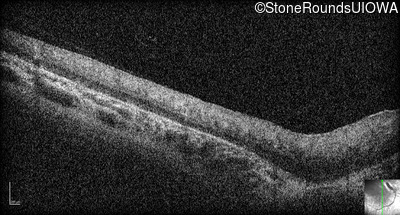

Optical Coherence Tomography - Right - No Light Perception

Exemplar / OCT Stack